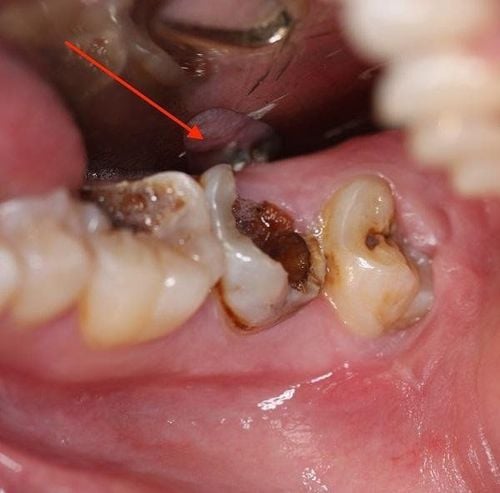

2. Như thế nào là răng sâu bị vỡ chỉ còn lại chân răng?

Sâu răng là tình trạng tổ chức cứng của răng bị tấn công, tiêu dần đi và tạo lỗ trên mặt răng. Tình trạng sâu răng diễn biến theo từng giai đoạn. Sâu răng nhẹ khi răng xuất hiện những vết đen li ti và xuất hiện lỗ nhỏ trên mặt răng. Lỗ sâu to dần và những cơn đau nhức răng từ ít đến nhiều bắt đầu xuất hiện. Những mảnh vỡ trên mặt răng ngày một lớn dần khi răng sâu nặng hơn. Sâu càng nặng, răng càng bị thương tổn nên vỡ mẻ càng nhiều hơn. Nếu không được khắc phục sớm, sâu răng sẽ tấn công hết lớp men và ngà răng ở phần thân răng và để lộ chân răng.